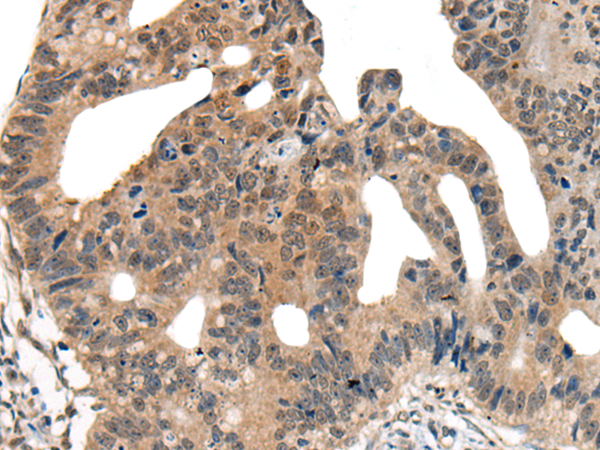

IHC positive control: |

Human liver cancer and human colorectal cancer |

IHC Recommend dilution: |

25-100 |